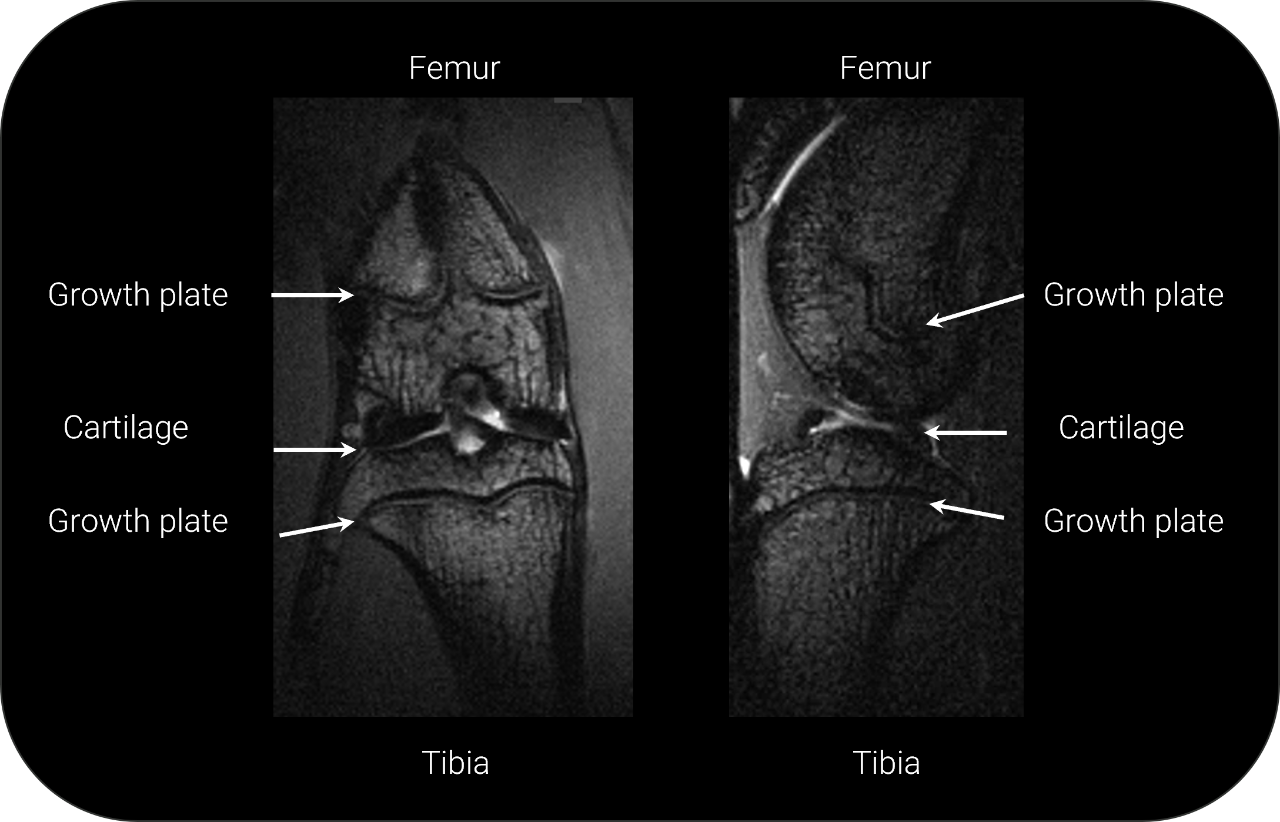

Knee Imaging at 3 T

Studies on structures very close to the surface are best imaged with planar surface coils, which can be placed at any location on the subject, such as here on a rat knee (20 mm planar surface coil was used for signal reception, 82 mm rat body volume coil was used for transmission)